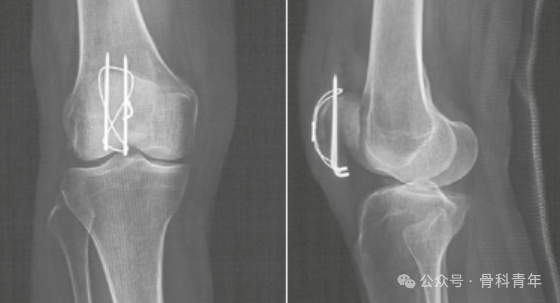

复位钳或巾钳临时维持复位后,经髌骨上缘或下缘,平行置入2枚2mm克氏针,克氏针置入点需距离髌骨前方皮质5mm,在冠状面与矢状面上于髌骨关节面平行。关于克氏针在冠状面上的位置,有学者认为克氏针应紧贴关节面已达到最好的张力带效果,也有学者认为克氏针应位于矢状面中后1/3处。不论哪种方式,克氏针均不可过于靠近髌骨前方,否则膝关节屈膝后后方骨折线张口,无法达到张力带目的。

除克氏针张力带外,对髌骨横行简单骨折,更多学者采用空心螺钉先将骨块复位加压,并通过空心钉孔置入钢丝,可以达到有效的张力带效果,并可避免克氏针滑出。